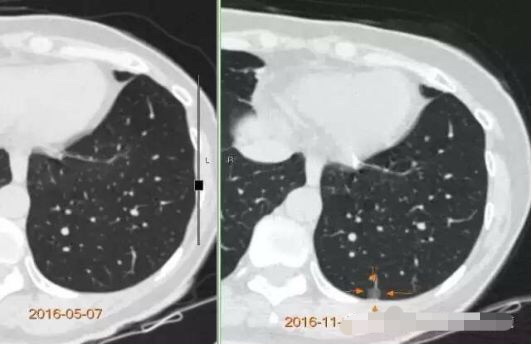

病例2

随访3年,GGO直径基本没有变化

2013年12月

2014年7月

2015年5月

2016年10月